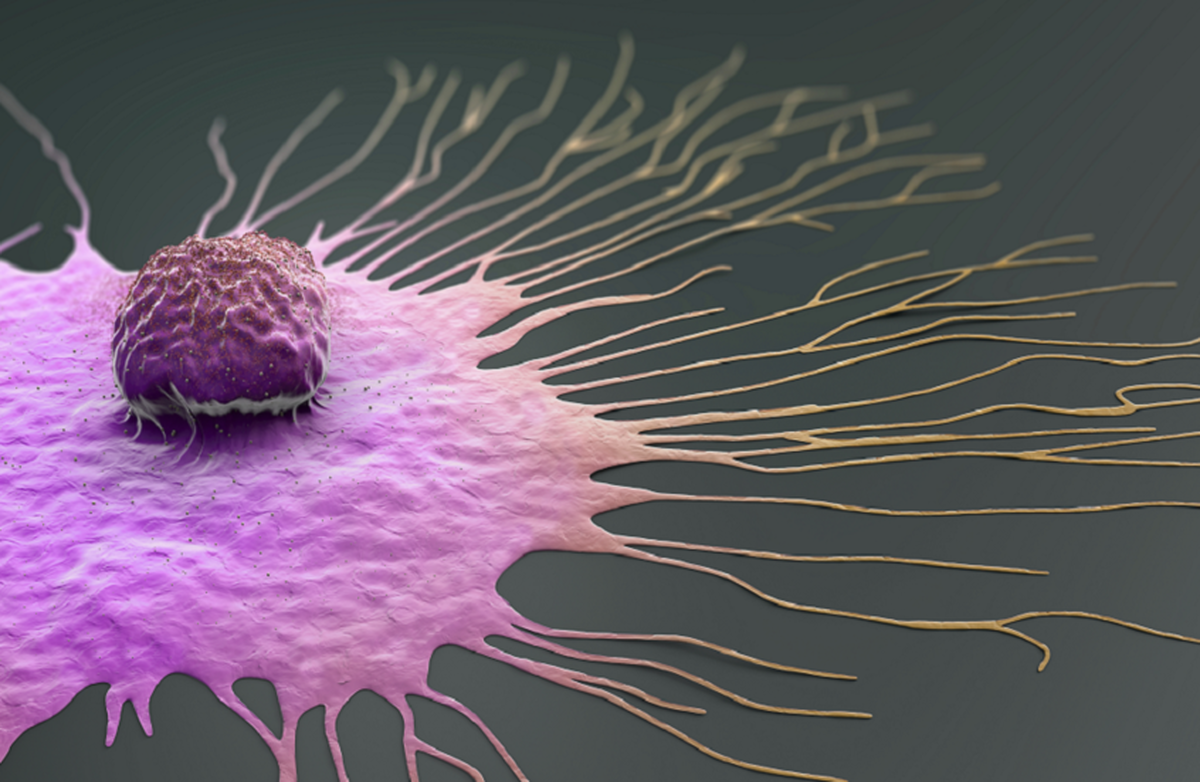

یک پیشرفت بزرگ در درمان سرطان سینه: کشف کلیدی برای جلوگیری از پیشرفت و گسترش بیماری

به گزارش مجله خبری نگار، این مطالعه نشان داد که سلولهای سرطانی با تأثیر بر متابولیسم - نحوه تولید انرژی توسط سلولها - نحوه عملکرد برخی از سلولهای ایمنی را تغییر میدهند و باعث میشوند این سلولهای ایمنی پروتئینی به نام اوراسیل ترشح کنند.

سلولهای سرطانی از این پروتئین به عنوان یک "داربست" استفاده میکنند که به آنها کمک میکند به اندامهای دیگر بچسبند و در آنها رشد کنند و راه را برای گسترش سرطان هموار کنند.

دانشمندان توانستند با مهار آنزیمی به نام یوریدین فسفوریلاز-۱ (UPP۱) که مسئول تولید اوراسیل است، از تشکیل این «داربست بیولوژیکی» در موشها جلوگیری کنند.

این مداخله، توانایی سیستم ایمنی بدن را برای حمله به سلولهای سرطانی و جلوگیری از گسترش آنها به مناطق جدید بدن بازیابی کرد.

تیم تحقیقاتی معتقد است که این کشف میتواند در آینده برای نظارت بر علائم گسترش سرطان با اندازهگیری سطح اوراسیل در خون و همچنین برای توسعه داروهایی که آنزیم UPP۱ را هدف قرار میدهند تا از گسترش آن قبل از شروع جلوگیری کنند، مورد استفاده قرار گیرد.

دکتر کاسی کلارک، نویسنده اصلی این مطالعه، گفت: «این تغییر در درک ما از متاستاز، نشاندهنده یک پیشرفت واقعی در تلاشهای ما برای نجات جان انسانها است. اگر بتوانیم این تغییرات را زود هدف قرار دهیم، میتوانیم پیشرفت سرطان را به طور کامل متوقف کنیم.»

دکتر کاترین الیوت از مرکز تحقیقات سرطان بریتانیا اظهار داشت: «گسترش سرطان بزرگترین چالش در درمان سرطان سینه است، به خصوص اگر پس از مدت زمان طولانی عود کند. این کشف به ما امید واقعی برای متوقف کردن زودهنگام آن میدهد.»